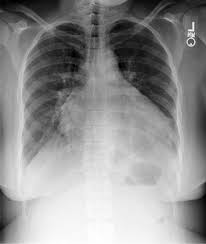

Cardiomegaly definition x ray. An enlarged heart cardiomegaly isn t a disease but rather a sign of another condition. Less severe forms of cardiomegaly are referred to as mild cardiomegaly. Maximal horizontal cardiac diameter. In equivocal cases the cardiothoracic ratio ctr can be easily calculated on a pa chest x ray.

Q fever endocarditis in hiv infected patient. It is not a disease but a sign of another condition. Chest x ray showed cardiomegaly and congestive heart failure. Cardiothoracic ratio is measured on a pa chest x ray and is the ratio of.

Cardiomegaly is easily visualized on chest x ray. At autopsy cardiomegaly with right atrial and ventricular dilation was identified. Therefore medications are prescribed to such affected individuals and they may have to take them for the rest of their lives. A useful measurement on x ray is the cardio thoracic ratio which is the transverse diameter of the heart compared with that of the thoracic cage these diameters are taken from pa chest x rays using the widest point of the chest.

Maximal horizontal thoracic diameter inner edge of ribs edge of pleura figure 2. X ray presentation of cardiomegaly most people are able to recover normal heart functions but only if the condition is detected early after which it is not possible to repair the damage. An x ray of the chest helps one to detect any kind of enlargement of the heart. Other findings on chest x ray can help to determine the specific chamber that is contributing most to the enlargement of the heart.

If the heart is enlarged on an x ray other tests will usually be needed to find the cause. Tap on off image to show hide findings. The ctr measures the width of the cardiac silhouette and the thoracic. X ray images help see the condition of the lungs and heart.

Cardiomegaly is an enlarged heart. In most cases merely eye balling a chest x ray will be sufficient in detecting cardiomegaly as the heart is either clearly normal in size or clearly abnormally enlarged. Other tests are then needed to diagnose the condition that s causing the heart to be enlarged.